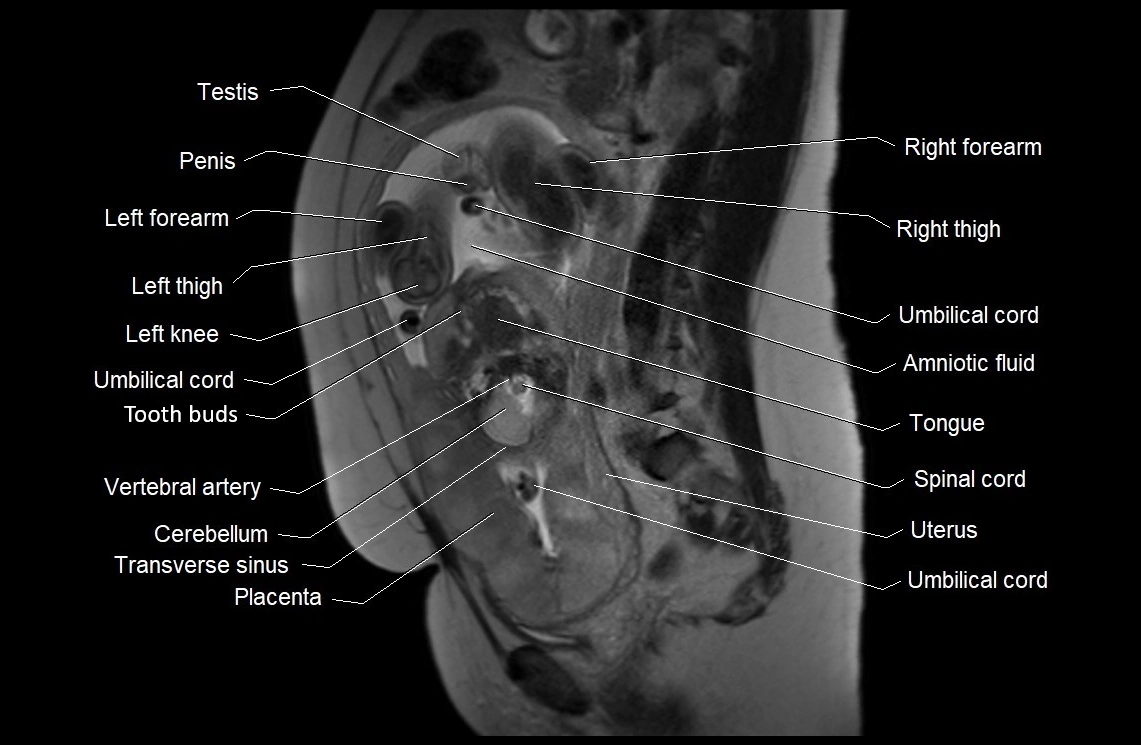

MRI Appearance

T2 HASTE (T2 GRE):

• Amniotic fluid shows very bright hyperintense signal

• Provides natural contrast against fetus and placenta

• Small particles (vernix) may appear as scattered hypointense foci within bright fluid